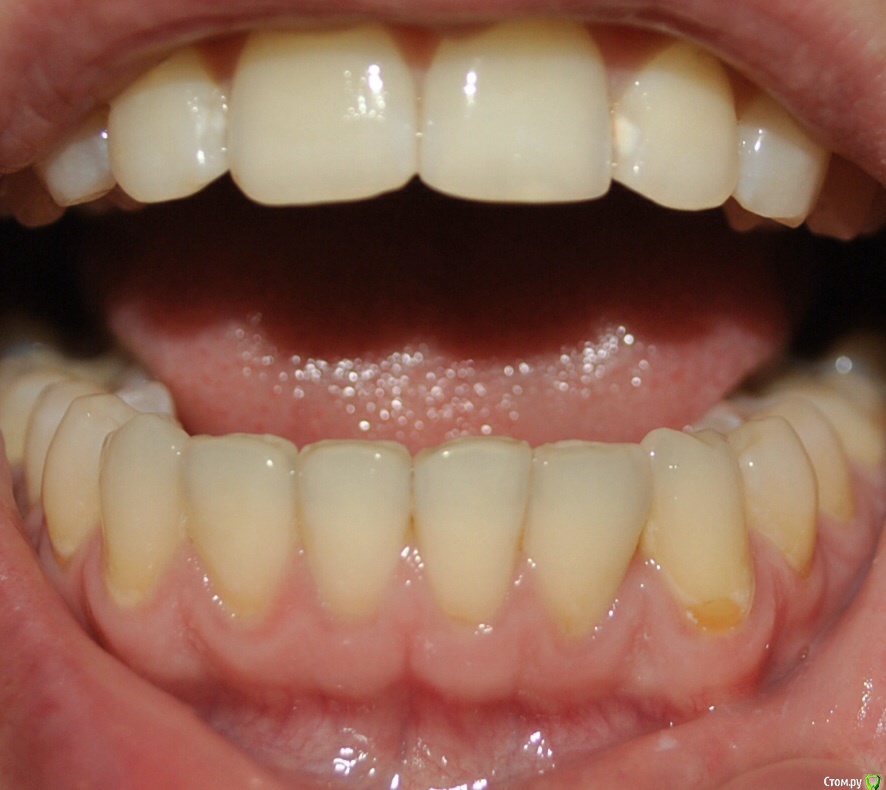

Алина-малина Опубликовано 4 августа, 2015 Поделиться Опубликовано 4 августа, 2015 Здравствуйте, уважаемые специалисты! Подскажите пожалуйста, как можно исправить эту ситуацию? Можно ли обойтись без брекетов? После ношения брекетов стал наклоняться клык вовнутрь. Стоит несемный ретейнер. Ортодонт утверждает что все в порядке и надо делать лоскутную операцию(( Ссылка на комментарий

Yana guapa Опубликовано 4 августа, 2015 Поделиться Опубликовано 4 августа, 2015 Подскажите пожалуйста, как можно исправить эту ситуацию? Можно ли обойтись без брекетов? После ношения брекетов стал наклоняться клык вовнутрь. если клык стал уходить во внутрь - значит что то его туда толкает. как правило, верхний клык (его позиция и наклон). За какой срок произошло изменение после снятие брекетов? Если реально беспокоит - то повторное ношение брекетов с правильным конечным взаимоотношением зубов (если это возможно сделать в силу различных факторов ). Ссылка на комментарий

Алина-малина Опубликовано 15 августа, 2015 Автор Поделиться Опубликовано 15 августа, 2015 Спасибо что ответили. Клык стал уходить через пол года после снятия. Брекеты носила 8 месяцев. Неужели теперь снова брекеты??? Возможно ли хотя бы на одну челюсть? Ссылка на комментарий

Yana guapa Опубликовано 15 августа, 2015 Поделиться Опубликовано 15 августа, 2015 Спасибо что ответили. Клык стал уходить через пол года после снятия. Брекеты носила 8 месяцев. Неужели теперь снова брекеты??? Возможно ли хотя бы на одну челюсть?если на одну челюсть - то и исправится на одной. логично же. а если у Вас на двух челюстях неровно стоят клыки - то на две и ставить надо. чудес не бывает. Вначале выровнять верхнюю, и тогда появится возможность выровнять нижнюю челюсть Ссылка на комментарий